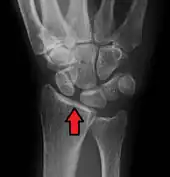

Scapholunate ligament disruption associated with a Colles' fracture

Rupture of the scapholunate ligament causes scapholunate instability, which, if untreated, will eventually cause a predictable pattern of wrist osteoarthritis called scapholunate advanced collapse (SLAC).[2]

Complete rupture of this ligament leads to wrist instability. The main type of such instability is dorsal intercalated segment instability (DISI) deformity, where the lunate angulates to the posterior side of the hand.[4][5]